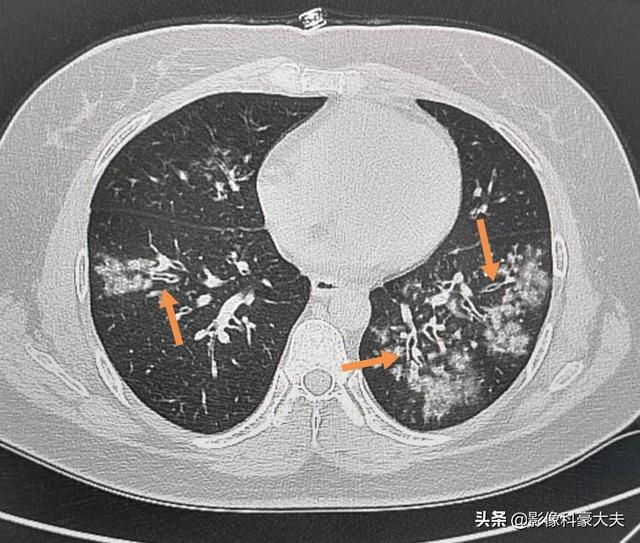

C'est le cas de cette jeune femme qui toussait et avait de la fièvre avec peu d'expectorations et qui ne se portait pas bien avec les médicaments contre le rhume et la grippe. Un scanner a été réalisé et a révéléL'inflammation par plaques dans les deux poumons avec de multiples petits épaississements de la paroi des voies respiratoires et une distribution centrée des foyers dans les voies respiratoires correspond à une pneumonie à Mycoplasma et non à une pneumonie néocoronarienne.